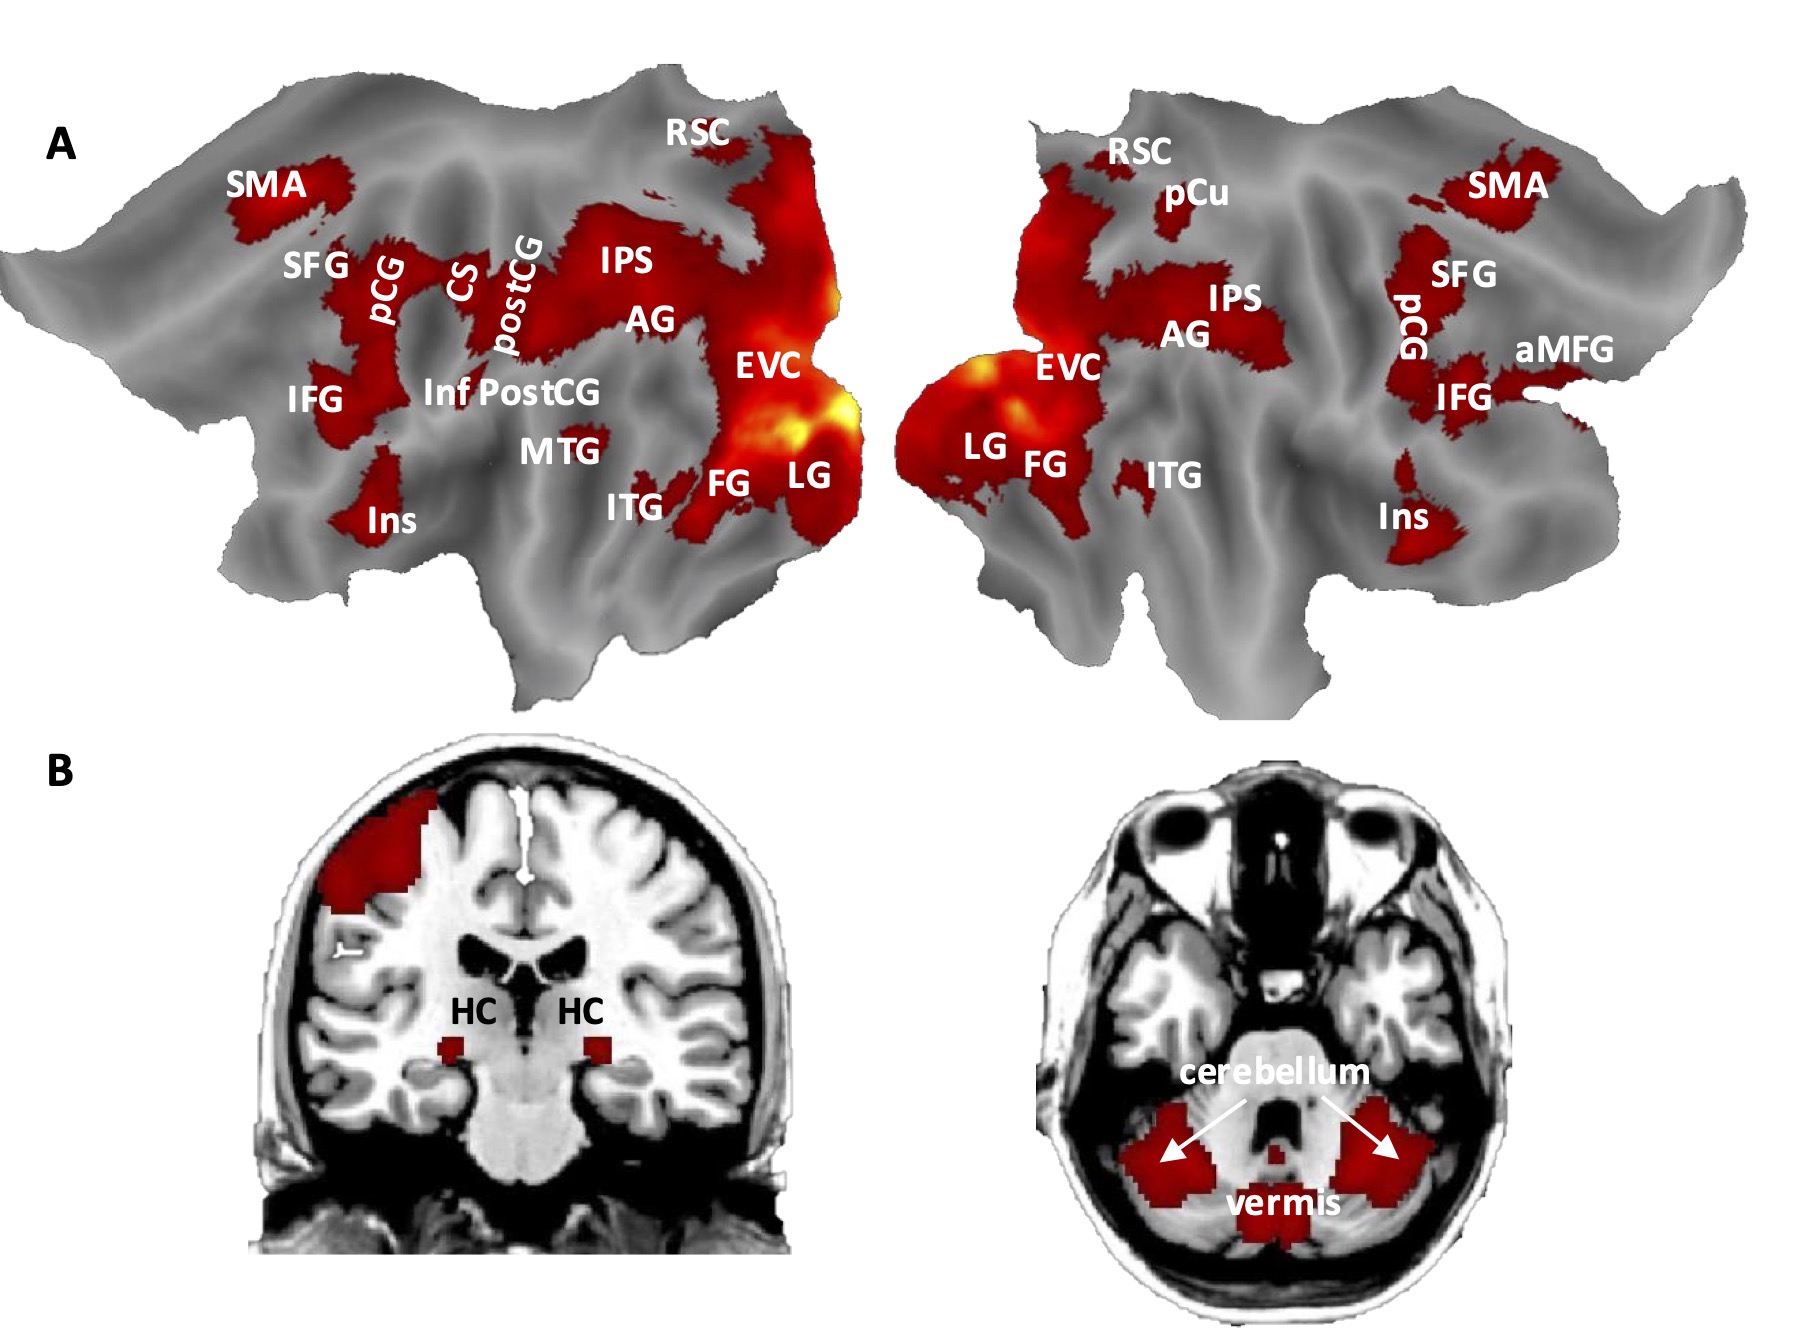

The results of our first functional magnetic resonance imaging study provide new insights into how personal events are temporally organized in the human brain. In brief, we found that a distributed network of brain regions (i.e. occipital, temporal, parietal, frontal, and subcortical regions) is involved in mental projection across the past and future. Interestingly, we observed that most of these regions exhibited neural modulation as a function of life span and/or as a function of compatibility with a back-to-front mental timeline, suggesting a key role for these regions in representing the temporal organization of personal events. Furthermore, the closer the personal events, the stronger the functional coupling between regions of the parietotemporal network and the visual cortex and hippocampus. Revealing the neural underpinnings of mental travel across past and future autobiographical events as a function of temporal reference and distance will significantly advance the field of neuropsychology of memory. Although several studies have investigated neuropsychological aspects of episodic autobiographical memory and episodic future thinking, little was known about the fine-grained spatiotemporal dynamics of mental travel prior to our study. Our results reveal a network of brain areas involved in mental projection across the past and future. These results would inform new investigations aimed at testing the causal contribution of these brain areas to the human ability to place oneself in the past and in the future.

Brain regions involved in mental travel across personal and public events